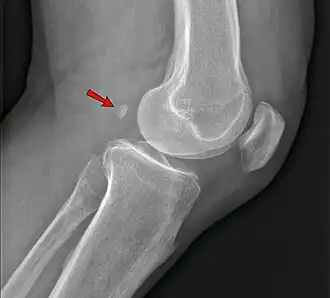

Фабелла — небольшая сесамовидная кость, обнаруженная у некоторых млекопитающих, встроенная в сухожилие боковой головки икроножной мышцы позади латерального мыщелка бедренной кости. Это дополнительная кость, анатомическая вариация, присутствующая у 39 % людей[1][2]. В редких случаях таких костей бывает две или три (fabella bi- или tripartita). Эту кость можно принять за дряблое тело или остеофит. Слово fabella — это латинское уменьшительное от слова faba, означающего «фасоль»[3].

Среди людей фабелла чаще встречается у мужчин, чем у женщин, и у пожилых по сравнению с более молодыми. Существуют большие региональные различия, при этом фабеллы чаще всего встречаются у людей, живущих в Азии и Океании, и наименее распространены у людей, живущих в Северной Америке и Африке. Двусторонние случаи (по одному на колено) более распространены, чем односторонние (по одному на человека), и в отдельных случаях фабеллы в равной степени могут присутствовать в правом или левом колене. Эти данные предполагают, что способность образовывать фабеллу может контролироваться генетически, но окостенение фабеллы может контролироваться окружающей средой[4].